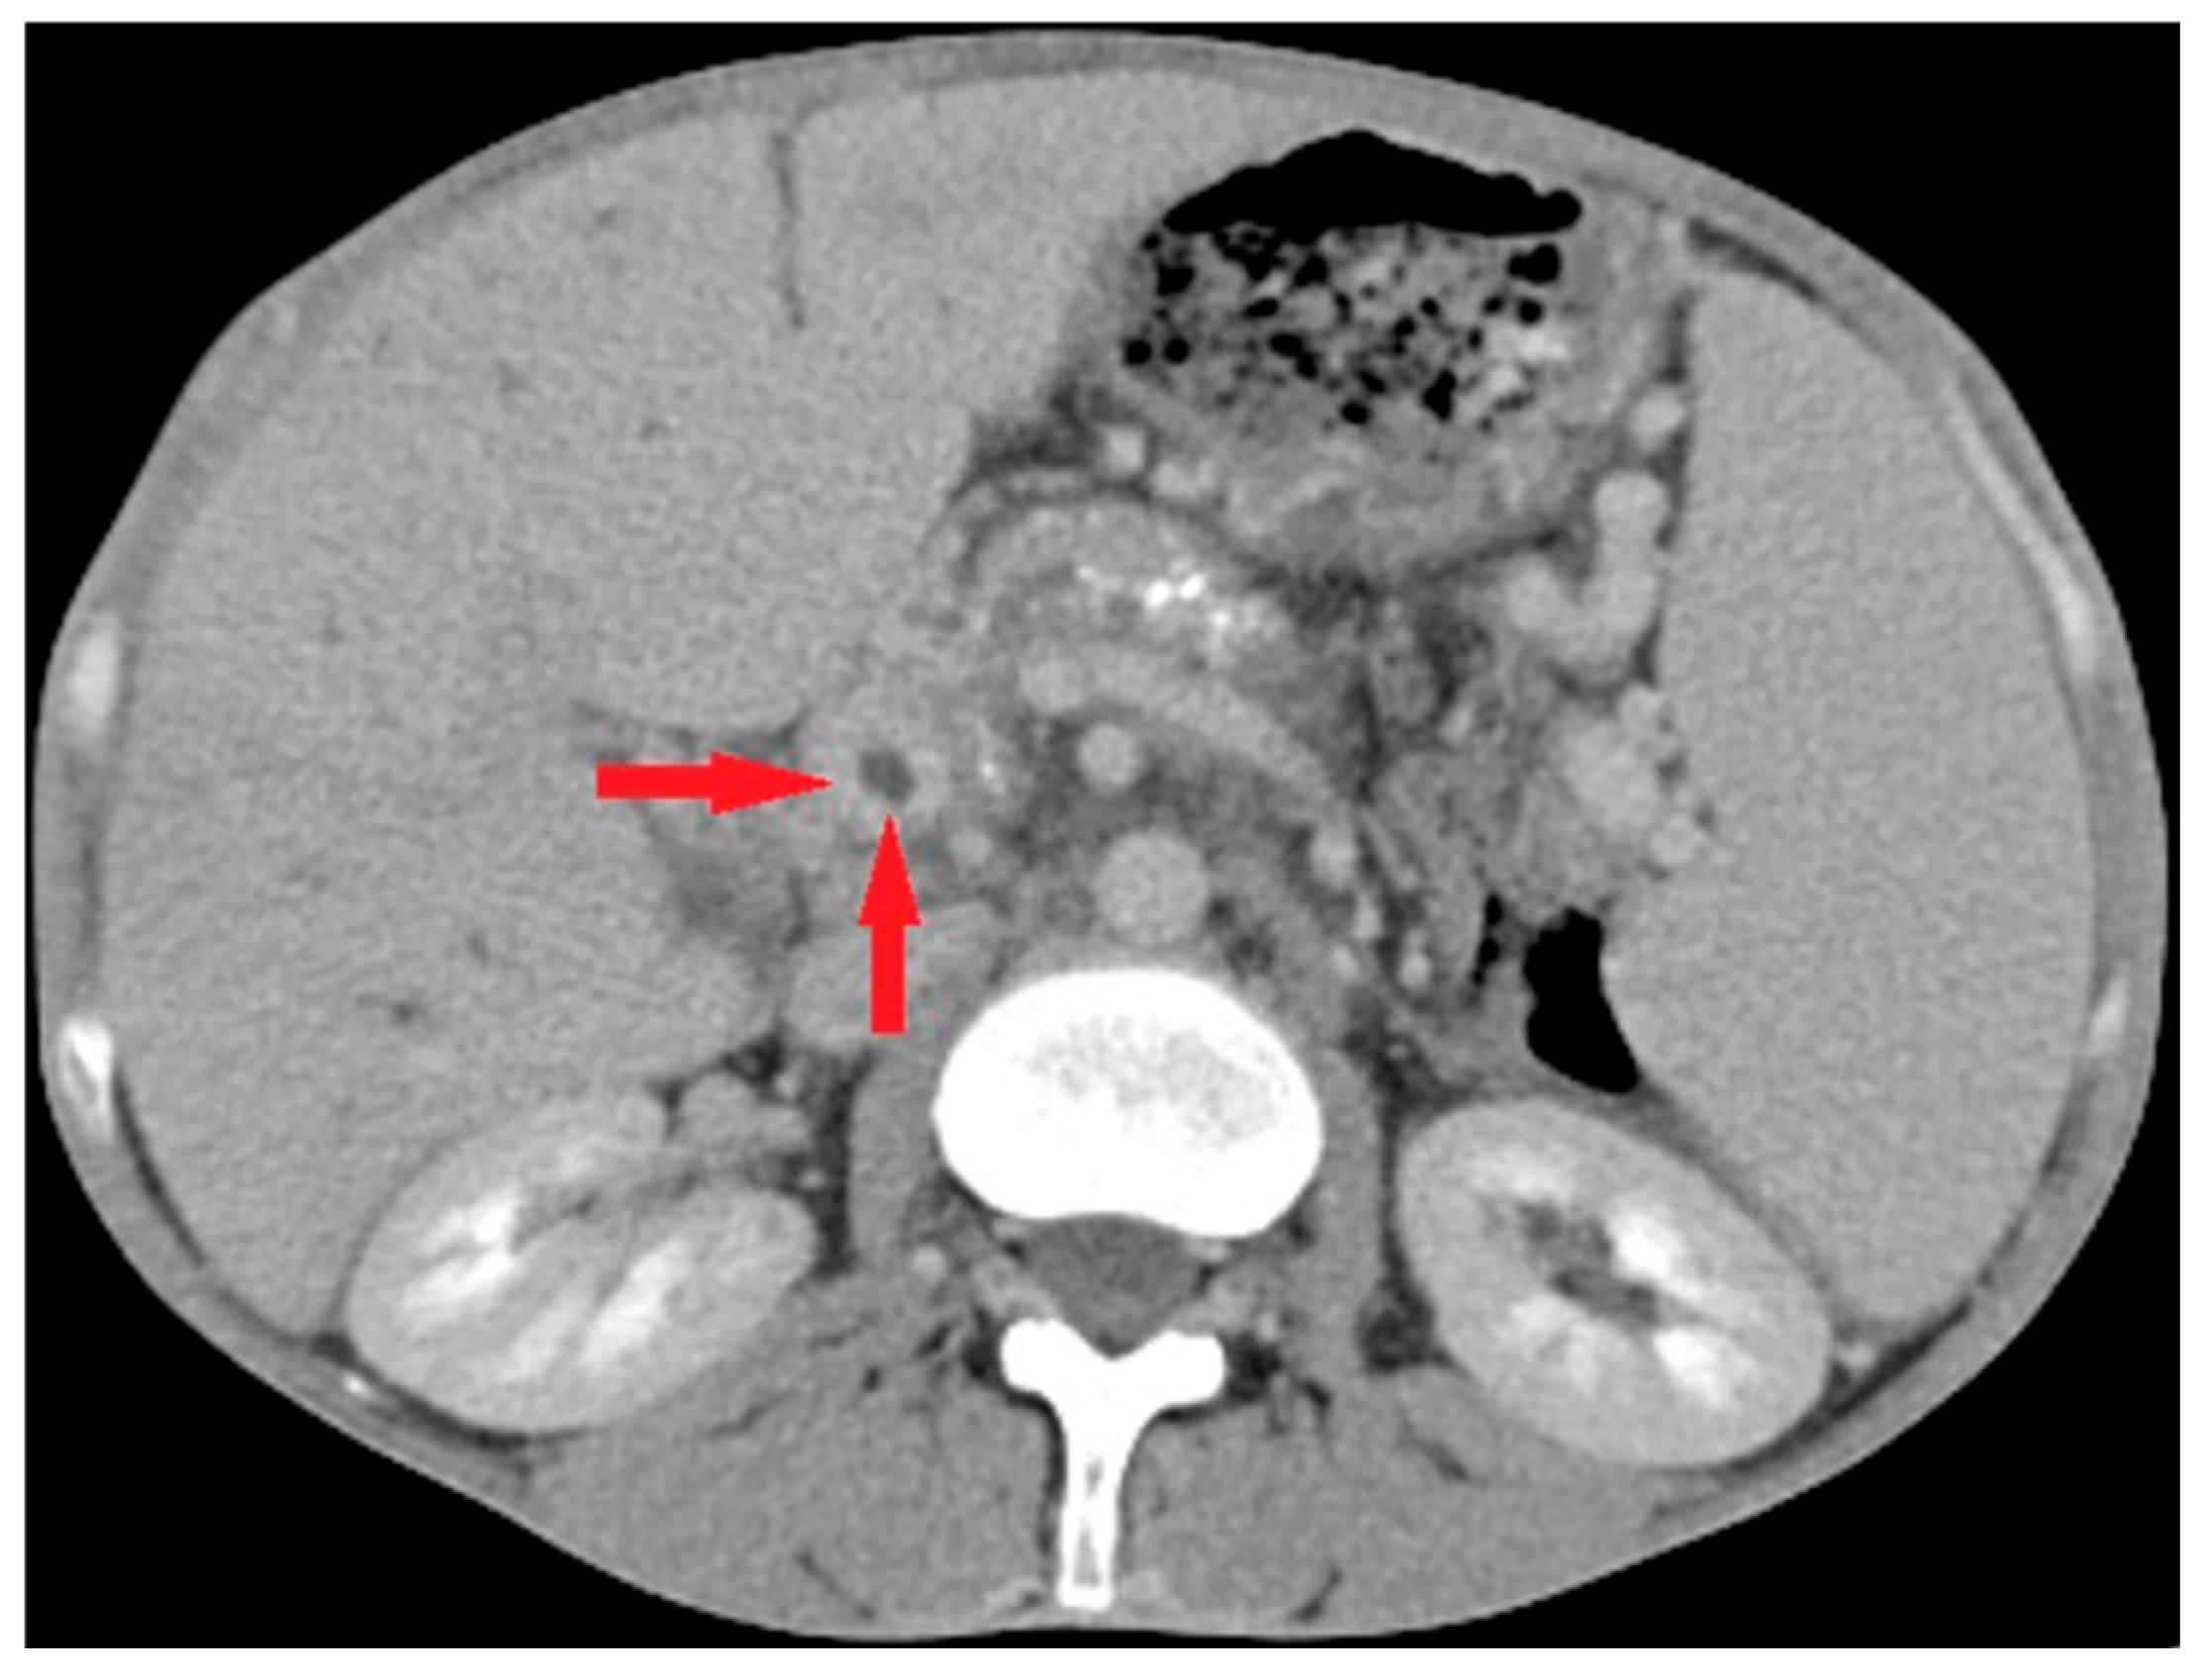

Imaging played a crucial role in diagnosing pylephlebitis, with computed tomography remaining the primary test for identifying this condition. Among the 14 patients evaluated by computed tomography (CT), 13 had PVT (Figure 2); in two cases (one with a ‘negative’ CT and one who did not undergo a CT scan examination), the diagnosis of PVT was based solely on ultrasound examination.

Figure 2. Abdominal CT scan in case of pylephlebitis. Legend: Suppurative portal vein thrombosis on CT scan seen as a central filling defect (red arrows); the illustration corresponds with case #11 described in Table 1 and Table 2.